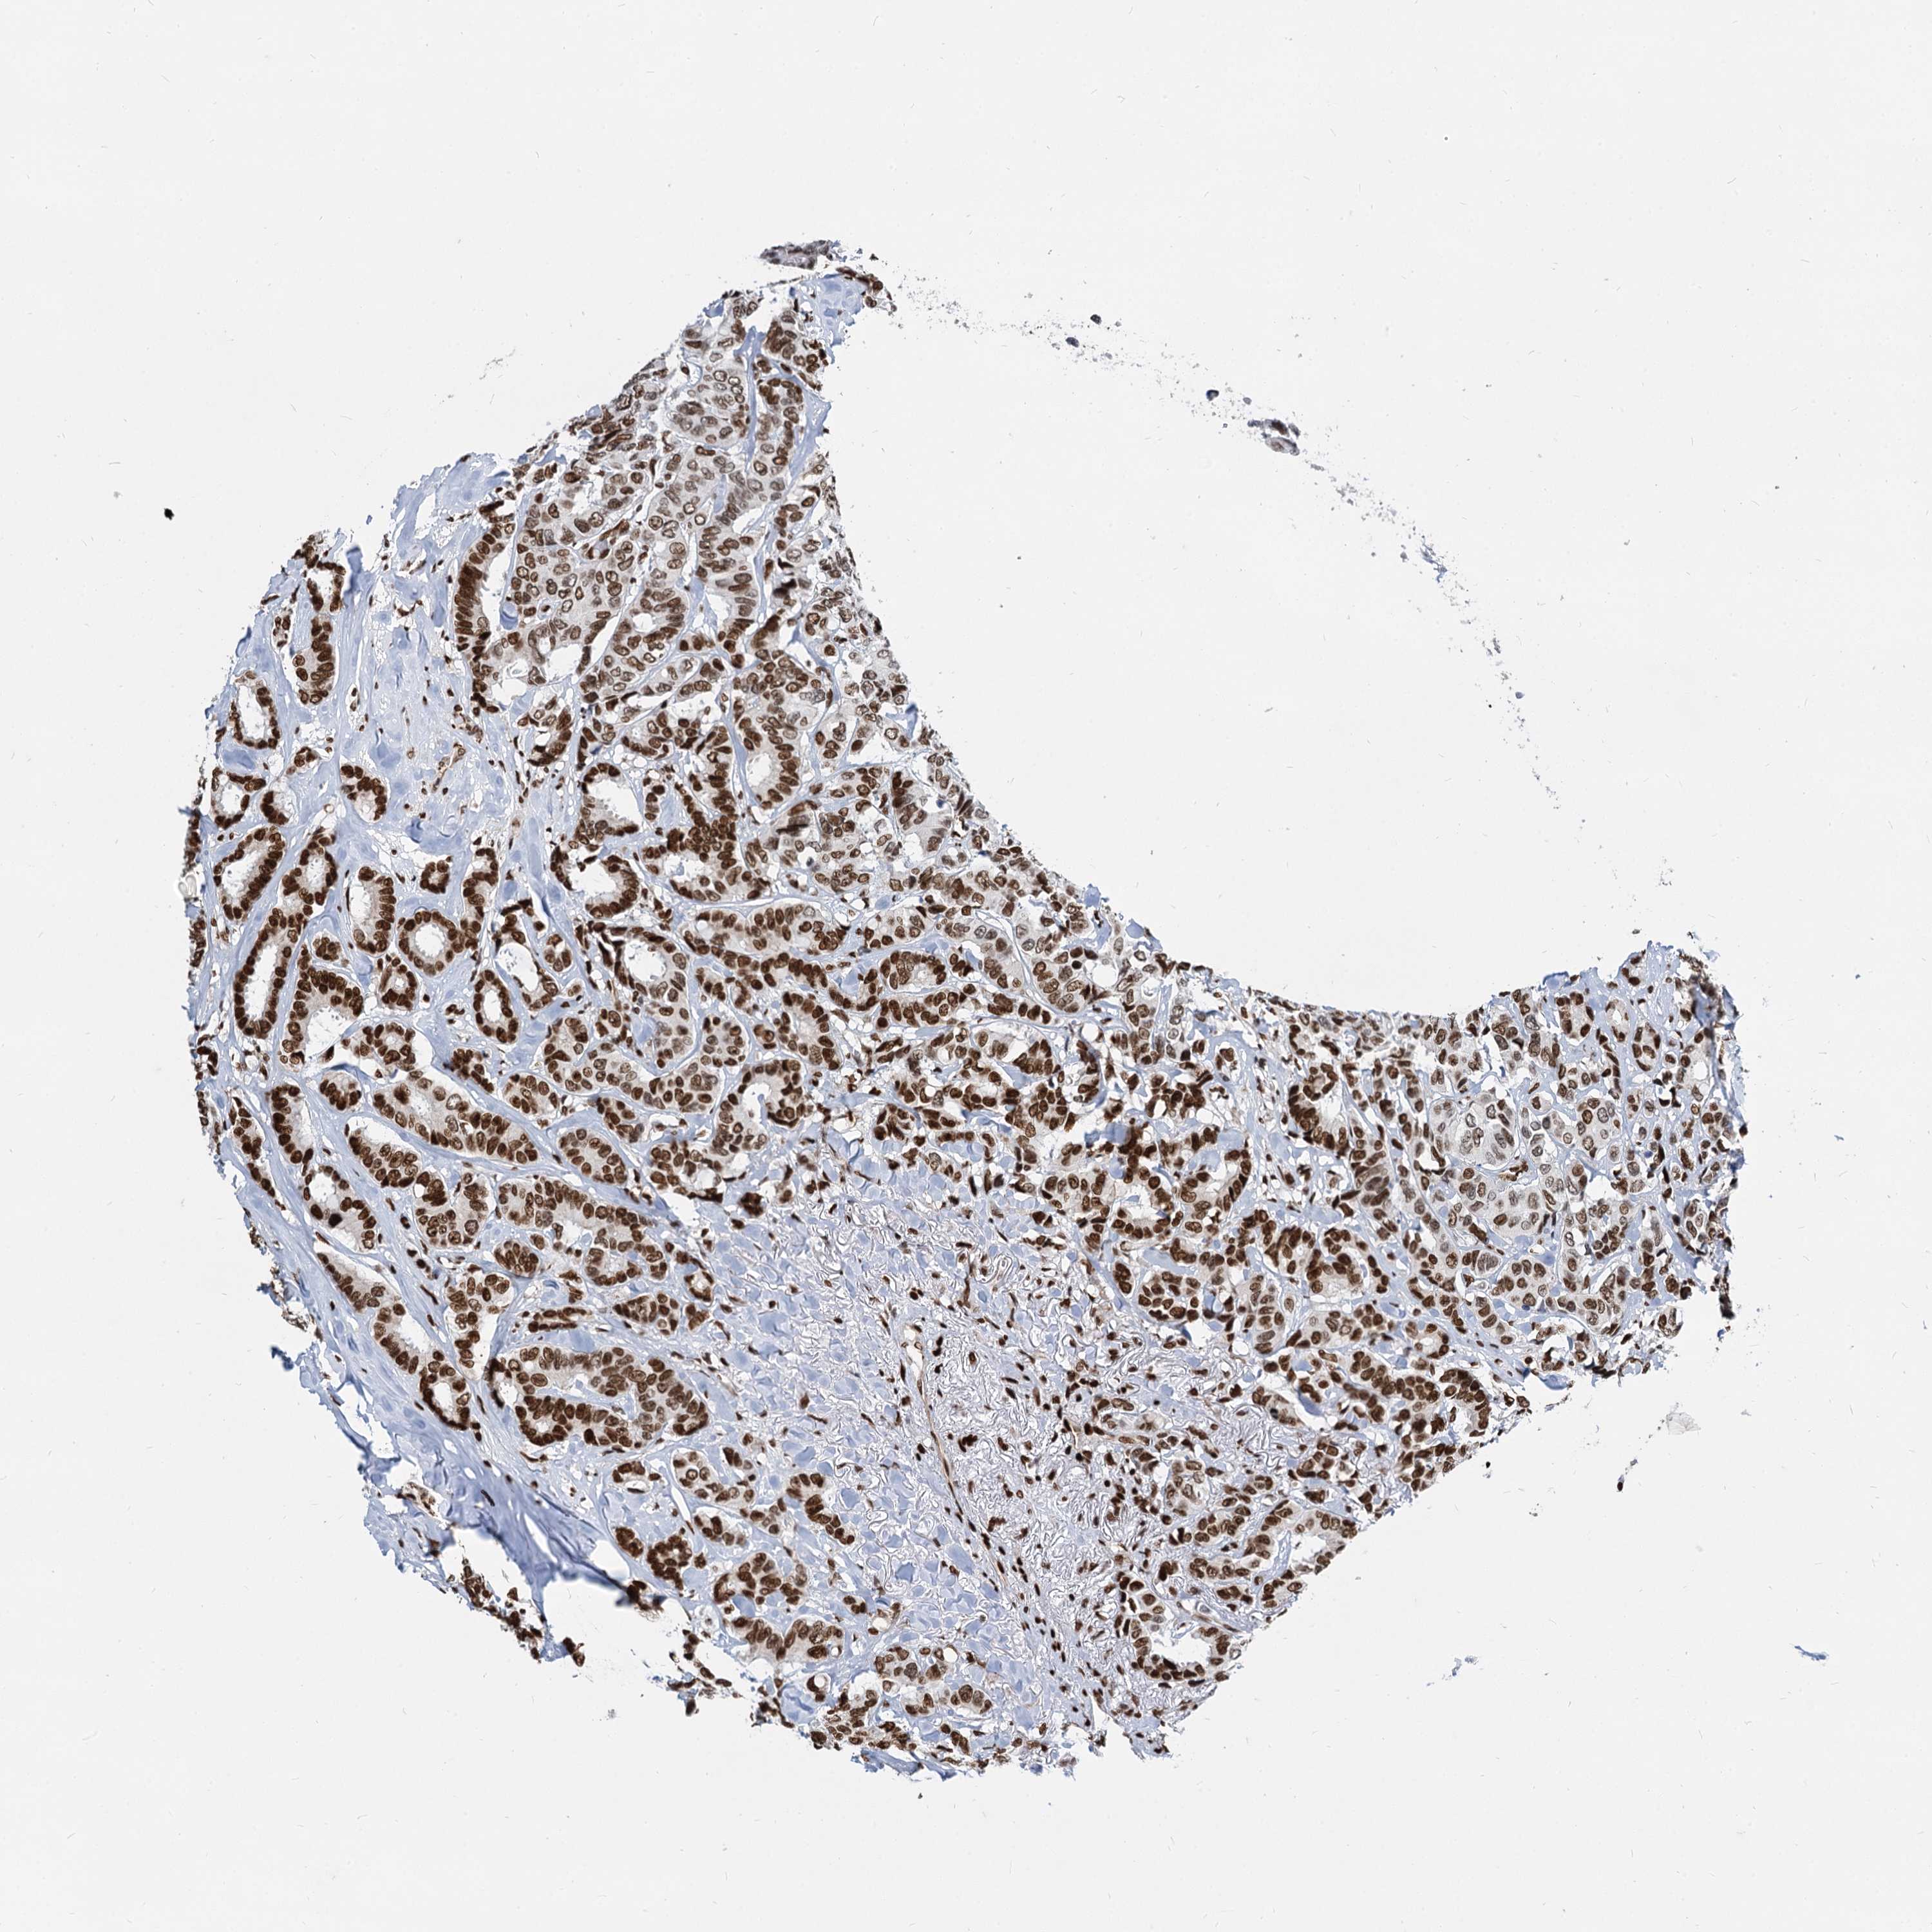

CANCER BREAST CANCER Show tissue menu

BRCA TCGA BRCA VALIDATION PROTEIN EXPRESSION

ANTIBODIES

AND

VALIDATION